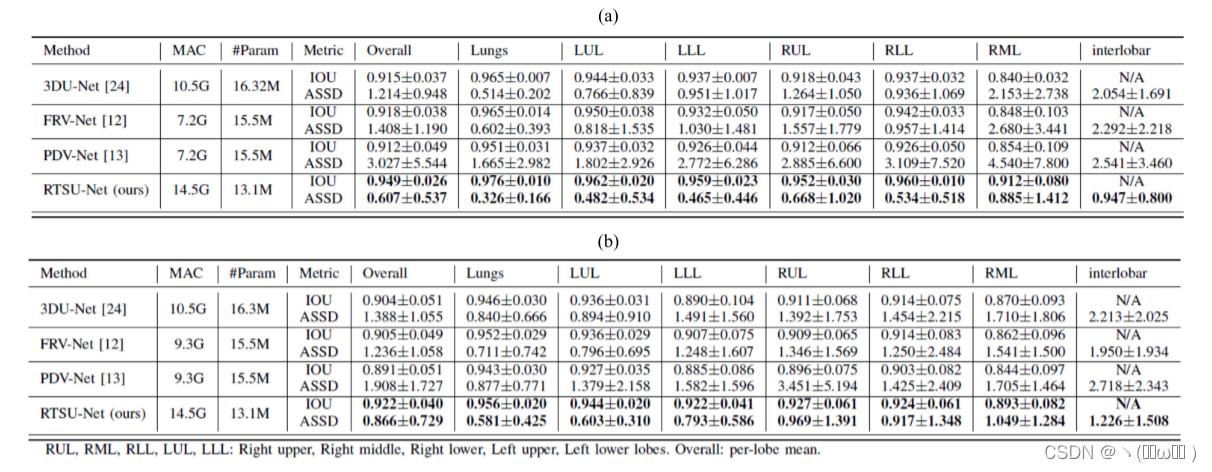

表 III 报告了两个数据集的定量结果。在所有测量中,所提出的方法在两个数据集(P < 0.01,Bonferroni 校正)上均显着优于基线方法和两种已发布的端到端叶分割方法。考虑到较小的标准偏差,我们的模型还表现出更稳健的性能。图 2 中提供了箱线图。这些图表明,对于 COVID-19 和 COPD 病例,右中叶是最难分割的,鉴于其已知的高度变化和形状差异,这不足为奇。事实上,小裂缝通常不完整甚至不存在。 RTSU-Net 在两个数据集上明显优于其他方法。还可以观察到,低 IOU 的异常值较少,表明 RTSU-Net 更健壮。

表 III:量化结果在慢性阻塞性肺病和COVID-19测试集。借据和ASSD(毫米)指标给出平均值±标准偏差。黑体表示结果明显好于其他与BONFERRONI调整(p < 0.01)

在计算效率方面,所提出的方法比基线方法消耗的内存更少,多加操作 (MAC) 仅略有增加。因此,我们得出结论,所提出的方法在没有引入大量计算开销的情况下优于其他方法。所提出的方法在测试时平均在 30 秒内处理一次扫描,其中大约 20 秒用于模型推理,其余时间用于预处理和后处理。